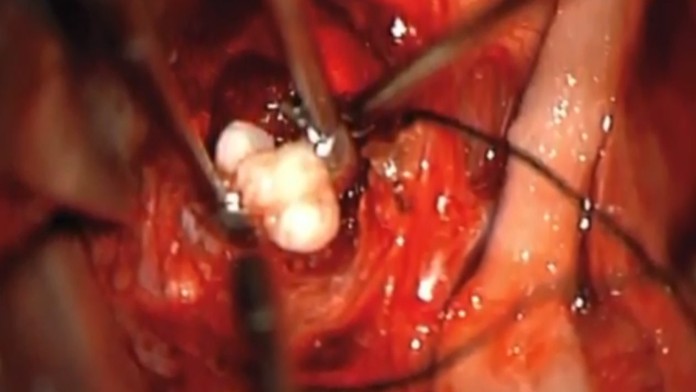

Zuby v nádore sú niečím veľmi jedinečným a ojedinelým. Lekári v Marylande diagnostikovali malému len štvormesačnému chlapčekovi rakovinu. Nádor v jeho mozgu mal 4,1 cm x 4 cm x 3,5 cm. Zistili to vďaka testom, ktoré preukázali, že bábätku sa hlava zväčšuje príliš rýchlo.

Chlapčeka operovali a v nádore našli niečo veľmi vzácne. Vyrastali z neho zuby. „Zuby v akomkoľvek druhu nádoru v mozgu teda nevidíme každý deň. A v kraniofaryngióme už vôbec," povedal neurochirurg Narlin Beaty, ktorý operoval. Podľa Metro.co.uk je už chlapček v poriadku a je zdravý.